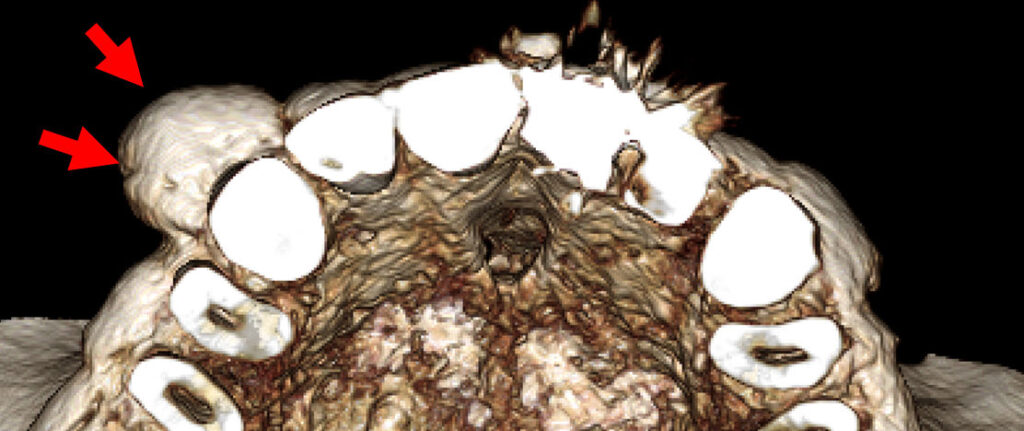

8-year-old boy with unusually shaped incisors and missing teeth

An 8-year-old boy was referred to a pediatric dentist because of the unusual shape of his mandibular incisors and several missing teeth.